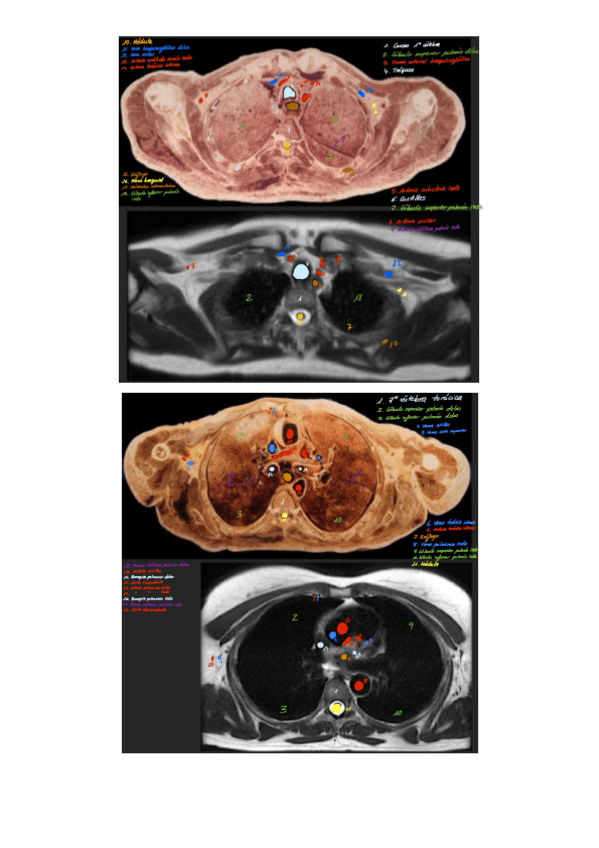

Imagenes-de-Torax-con-nombres.pdf

Practicas-12-y-13-resueltas-con-nombres.pdf

Imagenes-de-Torax-con-nombres-2.pdf